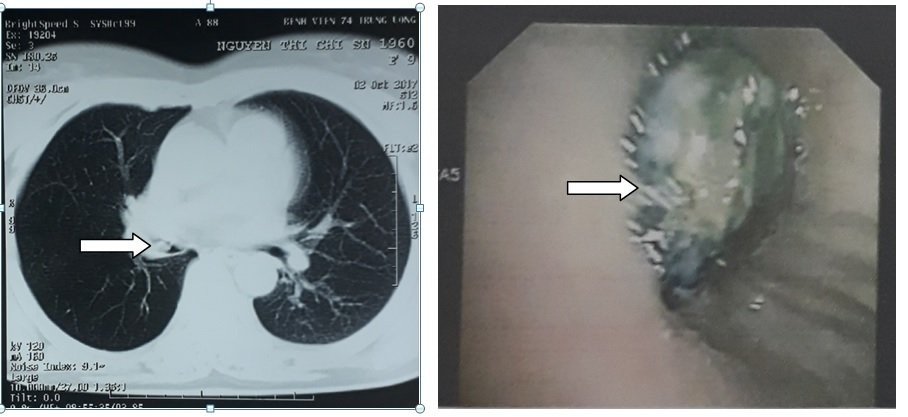

Hình ảnh CLVT nghi dị vật phế quản phải (hướng mũi tên ảnh trái) và hình ảnh dị vật ở phế quản trung gian phải trên nội soi phế quản ống mềm (ảnh phải).

Sau khi nhập viện, bác sĩ điều trị Nguyễn Xuân Thông chỉ định cho bệnh nhân chụp CT phổi và nội soi phế quản do nghi ngờ bệnh nhân viêm phổi do dị vật. Ngày 5/10, bác sĩ Nguyễn Văn Tình, Khoa Hồi sức cấp cứu - người trực tiếp tiến hành nội soi phế quản bằng ống mềm và phát hiện ra niêm mạc phế quả bệnh nhân bị xung huyết, lòng phế quản có hình ảnh dị vật. Bác sĩ Tình đã lấy ra dị vật là một hạt hồng xiêm ở vị trí phế quản trung gian bên phải. Sau 1 ngày, bệnh nhân hoàn toàn ổn định.